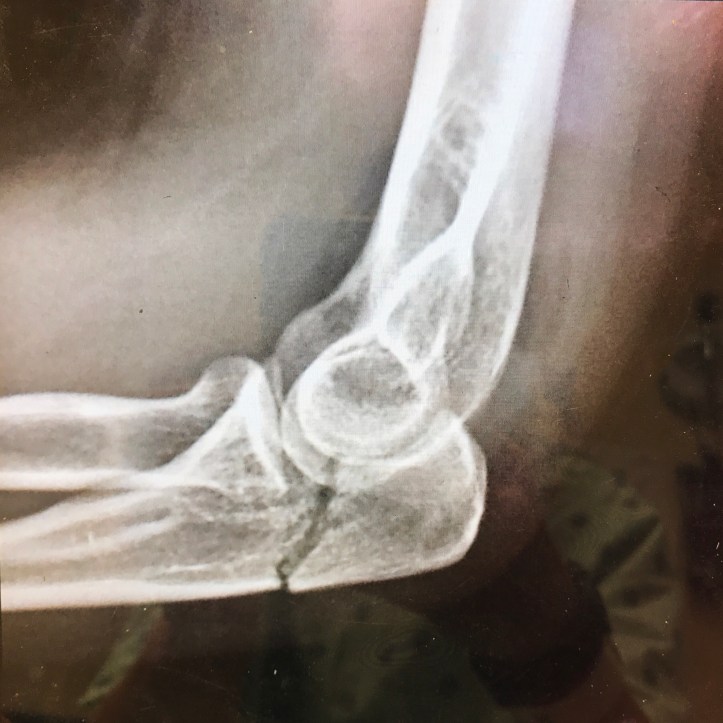

My stomach started to roil as I waited for the doctor to return with the results of the films. I heard a knock on the door jam. The doctor pushed aside the privacy curtain and walked in holding an iPad. He sat down on the stool, looked me in the eye, and said, “Where do you live?” And with that, I knew. That’s a question you ask someone with a broken elbow who needs further medical attention. I said as much out loud, and he confirmed my suspicions by scooting forward and showing me the films (top picture) that clearly showed a fracture line running through the head of my ulnar bone and about a quarter of an inch into my elbow joint. Because of the joint involvement, he urged me to see an orthopedic surgeon to determine if more specialized treatment would be in order. For the time being, he fit me in a splint and supplied me with a supremely uncomfortable sling. I shared my desire to walk the remaining AT miles necessary to bring my total to 1,000. He said, “Sure, go ahead and hike 10 miles. You can do it this afternoon if you like; it’s not your leg that’s broken. Just don’t fall.”